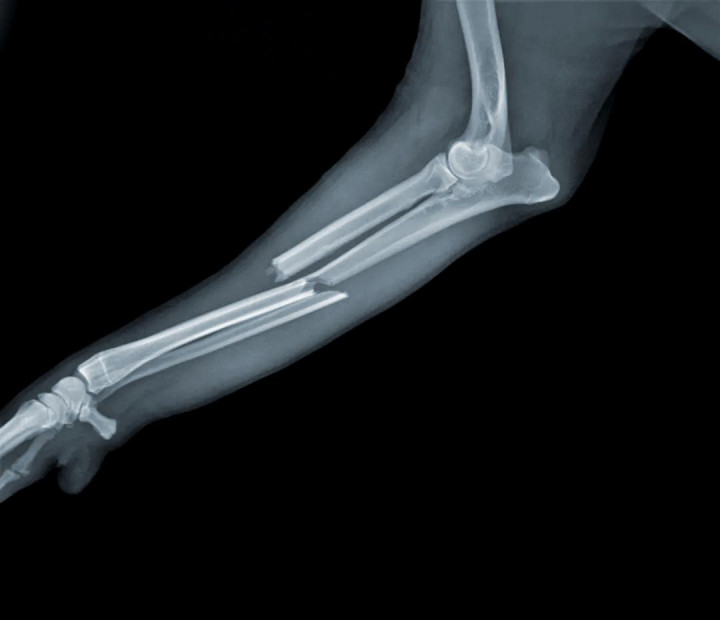

其次因为血压降低、血脂和血糖代谢速度减缓,骨骼无法获取足够的能量,会出现骨密度比一般人更低的情况,也就是骨质疏松。

没有强壮的骨骼支撑,身体出现骨折的可能性也会大幅度提升。

(古代太监更容易骨折)